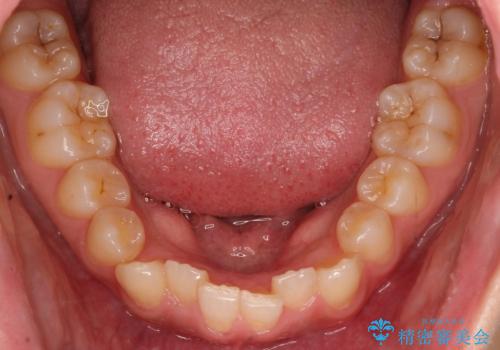

- 前歯のガタガタを主訴に来院された患者様です。

八重歯になっており、下顎の前歯が上顎の前歯に隠れてしまう、ディープバイトという状態でした。

インビザラインを使用して矯正する計画としました。